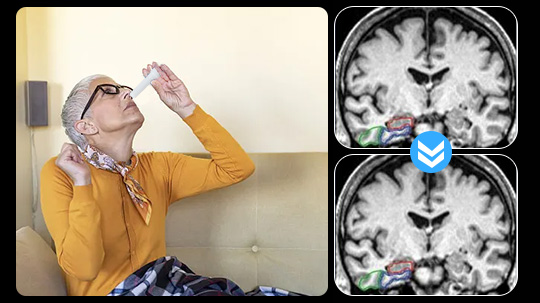

Above: A 68-year-old woman with a 10-year history of cognitive issues. Previous PET scans showed significant metabolic decline, indicating Alzheimer’s.